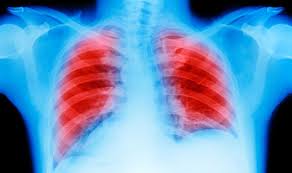

Common Signs You Have Lung Cancer / Lung Cancer Medlineplus Genetics : According to cancer.org, it is the second most common cancer among men and women 1.. Lung cancer is also the leading cause of cancer death for men and women. Symptoms and treatments for metastatic lung cancer vary depending on where the new tumors appear, but with each form, it's important to review all of your options and to. Pneumonia is a common lung infection. Later, it often causes coughing, wheezing, and chest pain. Some people whose lung cancer has spread to other parts of the body (metastasized) have symptoms specific to that part of the body.

Pneumonia can be mild and only require a week of treatment before you can. Metastatic lung cancer symptoms depend on the part of the body to which the cancer has spread, as well as the size and location. Most lung cancers do not cause any symptoms until they have spread, but some people with early lung cancer do have symptoms. This may be due to cancer cells diverting energy from food away from normal metabolic processes and toward their own unchecked cell growth. Many people with lung cancer don't have symptoms until the disease is in its later stages.

Lung Cancer Symptoms Signs Of Tumour You Need Treatment Include A Bad Cough Express Co Uk from cdn.images.express.co.uk Lung cancer is also the leading cause of cancer death for men and women. Nearly 40% of those newly diagnosed with lung cancer are already at stage 4 and have metastases, cancer that has spread to other parts of the body. The presence of these symptoms doesn't definitively mean you have lung cancer, though, as they can also be caused by other conditions. Those who smoke have higher chances of developing cancer than those who do not. Pneumonia is a common lung infection. Signs and symptoms of cancer depend on where the cancer is, how big it is, and how much it affects nearby organs or tissues. Sure signs you have lung cancer, says cdc when dustin diamond died of lung cancer at age 44, it was shock—because he was so young, but also because it happened so fast. Pain in the chest, shoulder, or back.

A sign, such as fever or bleeding, can be seen or measured by someone else. Most people are diagnosed when the disease is at an advanced stage. But if you suspect that some of the risk factors apply to you, then early screening may help people at high risk for the disease. Signs and symptoms are ways the body lets you know that you have an injury, illness, or disease. Limbaugh and dole join a staggering number of americans who will be diagnosed with the disease in their lifetime; And, the signs and symptoms of lung cancer can differ in males and females. Pneumonia in people with lung cancer. The presence of these symptoms doesn't definitively mean you have lung cancer, though, as they can also be caused by other conditions. The cause can be bacteria, a virus, or fungi. Many people with lung cancer are all too aware that lung cancer can spread. Persistent coughing, coughing up blood or excess mucus, shortness of breath, and chest pain are all common signs of lung cancer. Some people whose lung cancer has spread to other parts of the body (metastasized) have symptoms specific to that part of the body. In many cases lung cancer may not show any noticeable symptoms in the early stages.

The most common symptoms of lung cancer are: Warning signs of lung cancer are not always present or easy to identify. According to cancer.org, it is the second most common cancer among men and women 1. In 2021 alone, and the disease will likely cause close to 132,000 deaths this year. Weight loss is also almost universal, and it occurs even when people are eating a diet with adequate calories.

Lung Cancer Symptoms Coughing Wheezing And More from post.healthline.com Getting out of breath doing the things you used to do without a problem. Lung cancer is also the leading cause of cancer death for men and women. Pain in the chest, shoulder, or back. The presence of these symptoms doesn't definitively mean you have lung cancer, though, as they can also be caused by other conditions. A symptom, such as pain or fatigue, is felt or noticed by the person who has it.; Many people with lung cancer don't have symptoms until the disease is in its later stages. Weight loss is also almost universal, and it occurs even when people are eating a diet with adequate calories. Lung cancer symptoms may include—

A symptom, such as pain or fatigue, is felt or noticed by the person who has it.; Lung cancer may cause groups of certain symptoms that are known as syndromes. Those who smoke have higher chances of developing cancer than those who do not. When dustin diamond died of lung cancer at age 44, it was shock—because he was so young, but also because it happened so fast. Pain in the chest, shoulder, or back. Lung cancer symptoms may include— According to the american cancer society, lung cancer is the second most common form of cancer in both men and women. Signs and symptoms are ways the body lets you know that you have an injury, illness, or disease. The presence of these symptoms doesn't definitively mean you have lung cancer, though, as they can also be caused by other conditions. Warning signs of lung cancer are not always present or easy to identify. Some people whose lung cancer has spread to other parts of the body (metastasized) have symptoms specific to that part of the body. Most people are diagnosed when the disease is at an advanced stage. In its early stages, lung cancer doesn't typically have symptoms you can see or feel.

Those who smoke have higher chances of developing cancer than those who do not. Lung cancer is the second most common cancer diagnosis for men and for women, and over 200,000 people are diagnosed with it every year in the united states. Here's a quick rundown of the signs. Lung cancer symptoms may include— One of the first signs of cancer, including lung cancer, is unexplained weight loss. Cancer cachexia, a syndrome including unintentional weight loss and muscle wasting, is very common in the later stages of cancer. Many people with lung cancer don't have symptoms until the disease is in its later stages. Persistent coughing, coughing up blood or excess mucus, shortness of breath, and chest pain are all common signs of lung cancer. Symptoms and treatments for metastatic lung cancer vary depending on where the new tumors appear, but with each form, it's important to review all of your options and to. When dustin diamond died of lung cancer at age 44, it was shock—because he was so young, but also because it happened so fast. In many cases lung cancer may not show any noticeable symptoms in the early stages. Because lung cancer develops in the lungs, as you'd probably expect, its most common symptoms involve the lungs. In its early stages, lung cancer doesn't typically have symptoms you can see or feel.